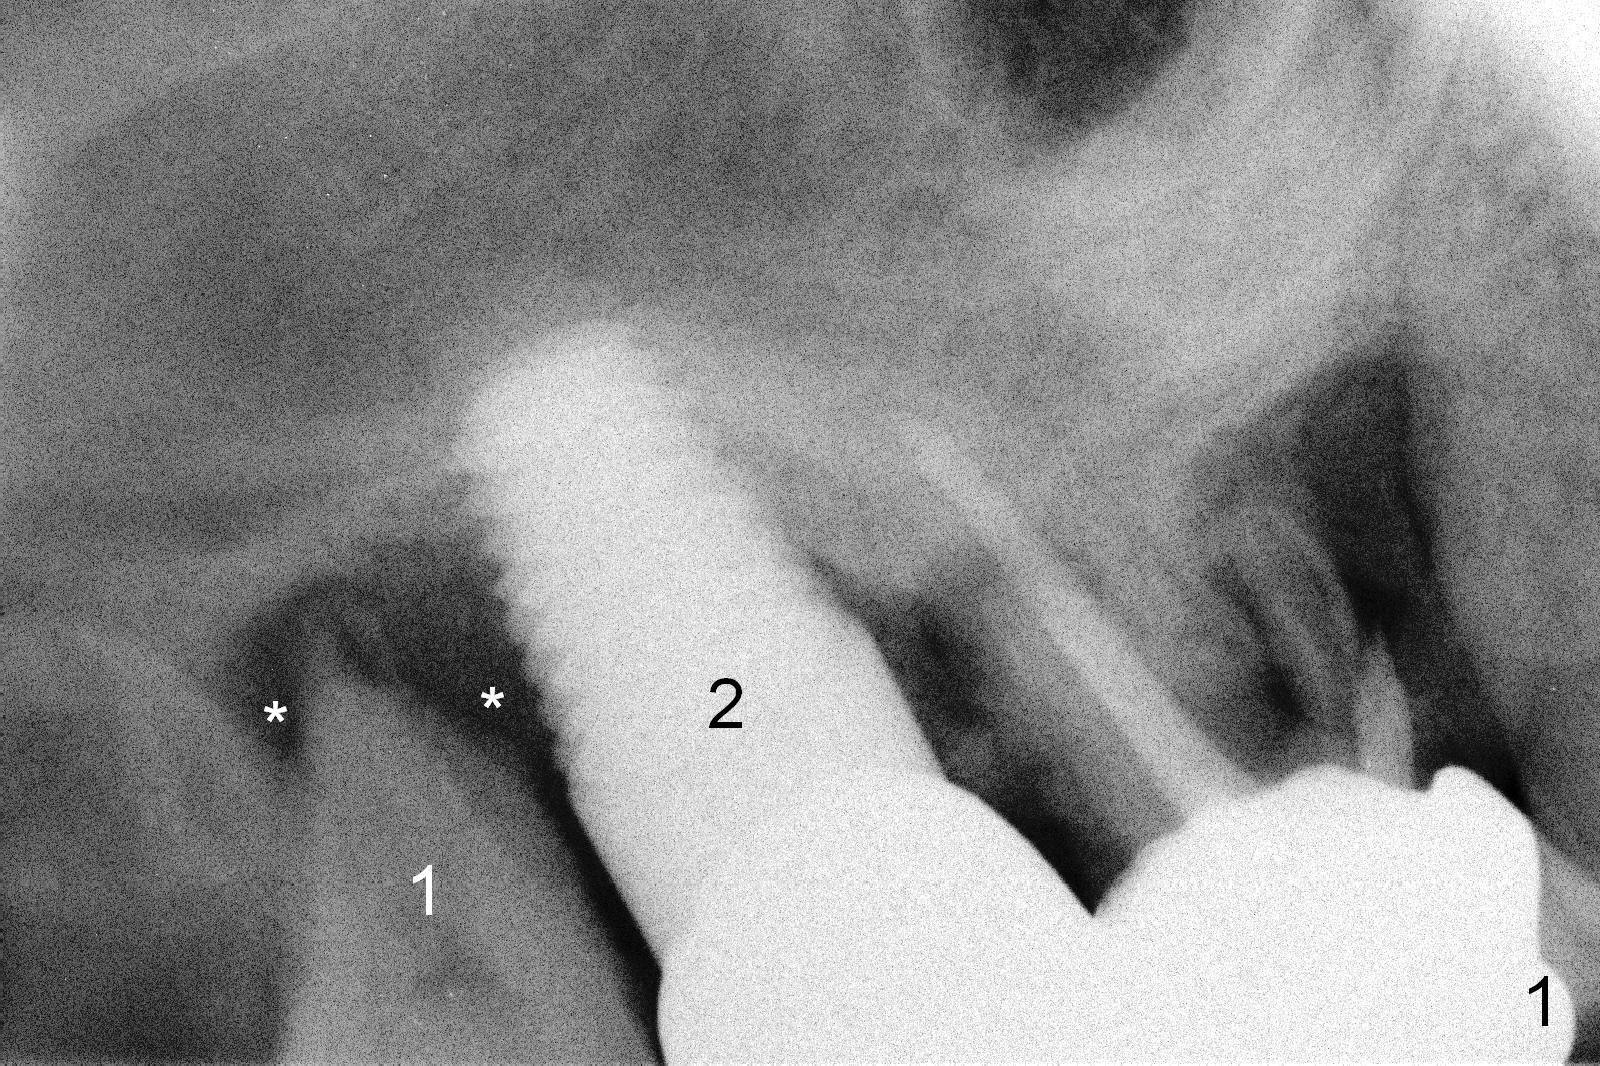

A 62-year-old man (CJ) had food impaction between the tooth #1 and the implant at #2 six months post cementation of the crown at #2. At the most recent visit (1.5 years post cementation), symptoms and signs of infection around the tooth #1 appear to get worse (Fig.1 *).  The patient accepted treatment plan (#1 extraction and immediate implant, Fig.2).

After extraction, the socket is curetted thoroughly, the implant threads cleaned with Titanium brush, and the wound treated with Metronidazole.  It appears that a 4.5x10 mm bone-level implant is appropriate for the site (Fig.2).